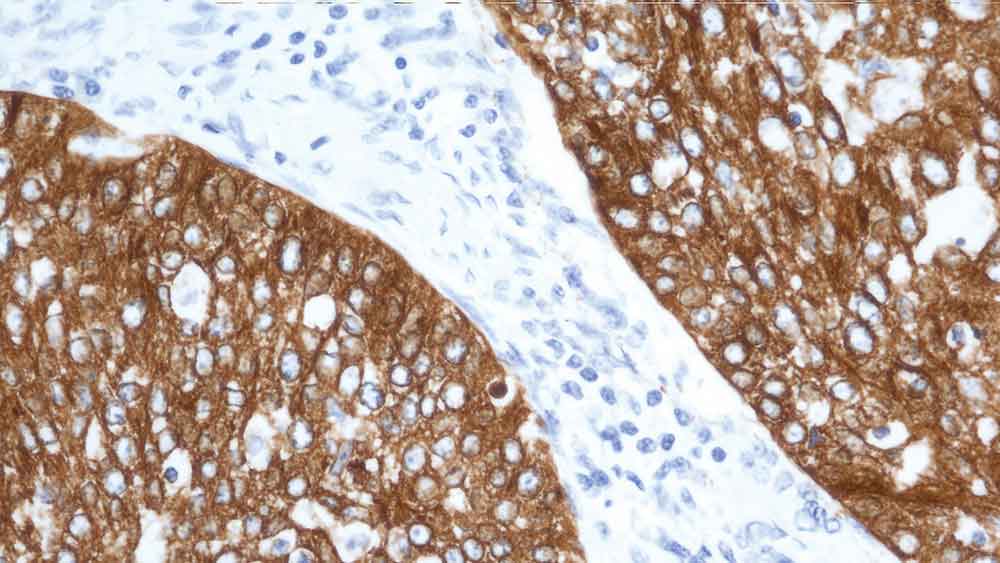

Human tonsil: immunohistochemical staining for CD56. Note the NK cells and CD4/CD8 double positive T cells show a weak to moderate and distinct membrane staining reaction while the majority of lymphocytes are unstained. CD56: clone CD564

The neural cell adhesion molecules are a family of closely-related cell surface glycoproteins thought to play a role in embryogenesis, development and contact-mediated interactions between neural cells. The CD56 antigen (NCAM) consists of four major isoforms generated by differential splicing of the RNA transcript from a single gene located on chromosome 5. The CD56 antigen is expressed on neurons, astrocytes, Schwann cells, NK cells and a subset of activated T lymphocytes.